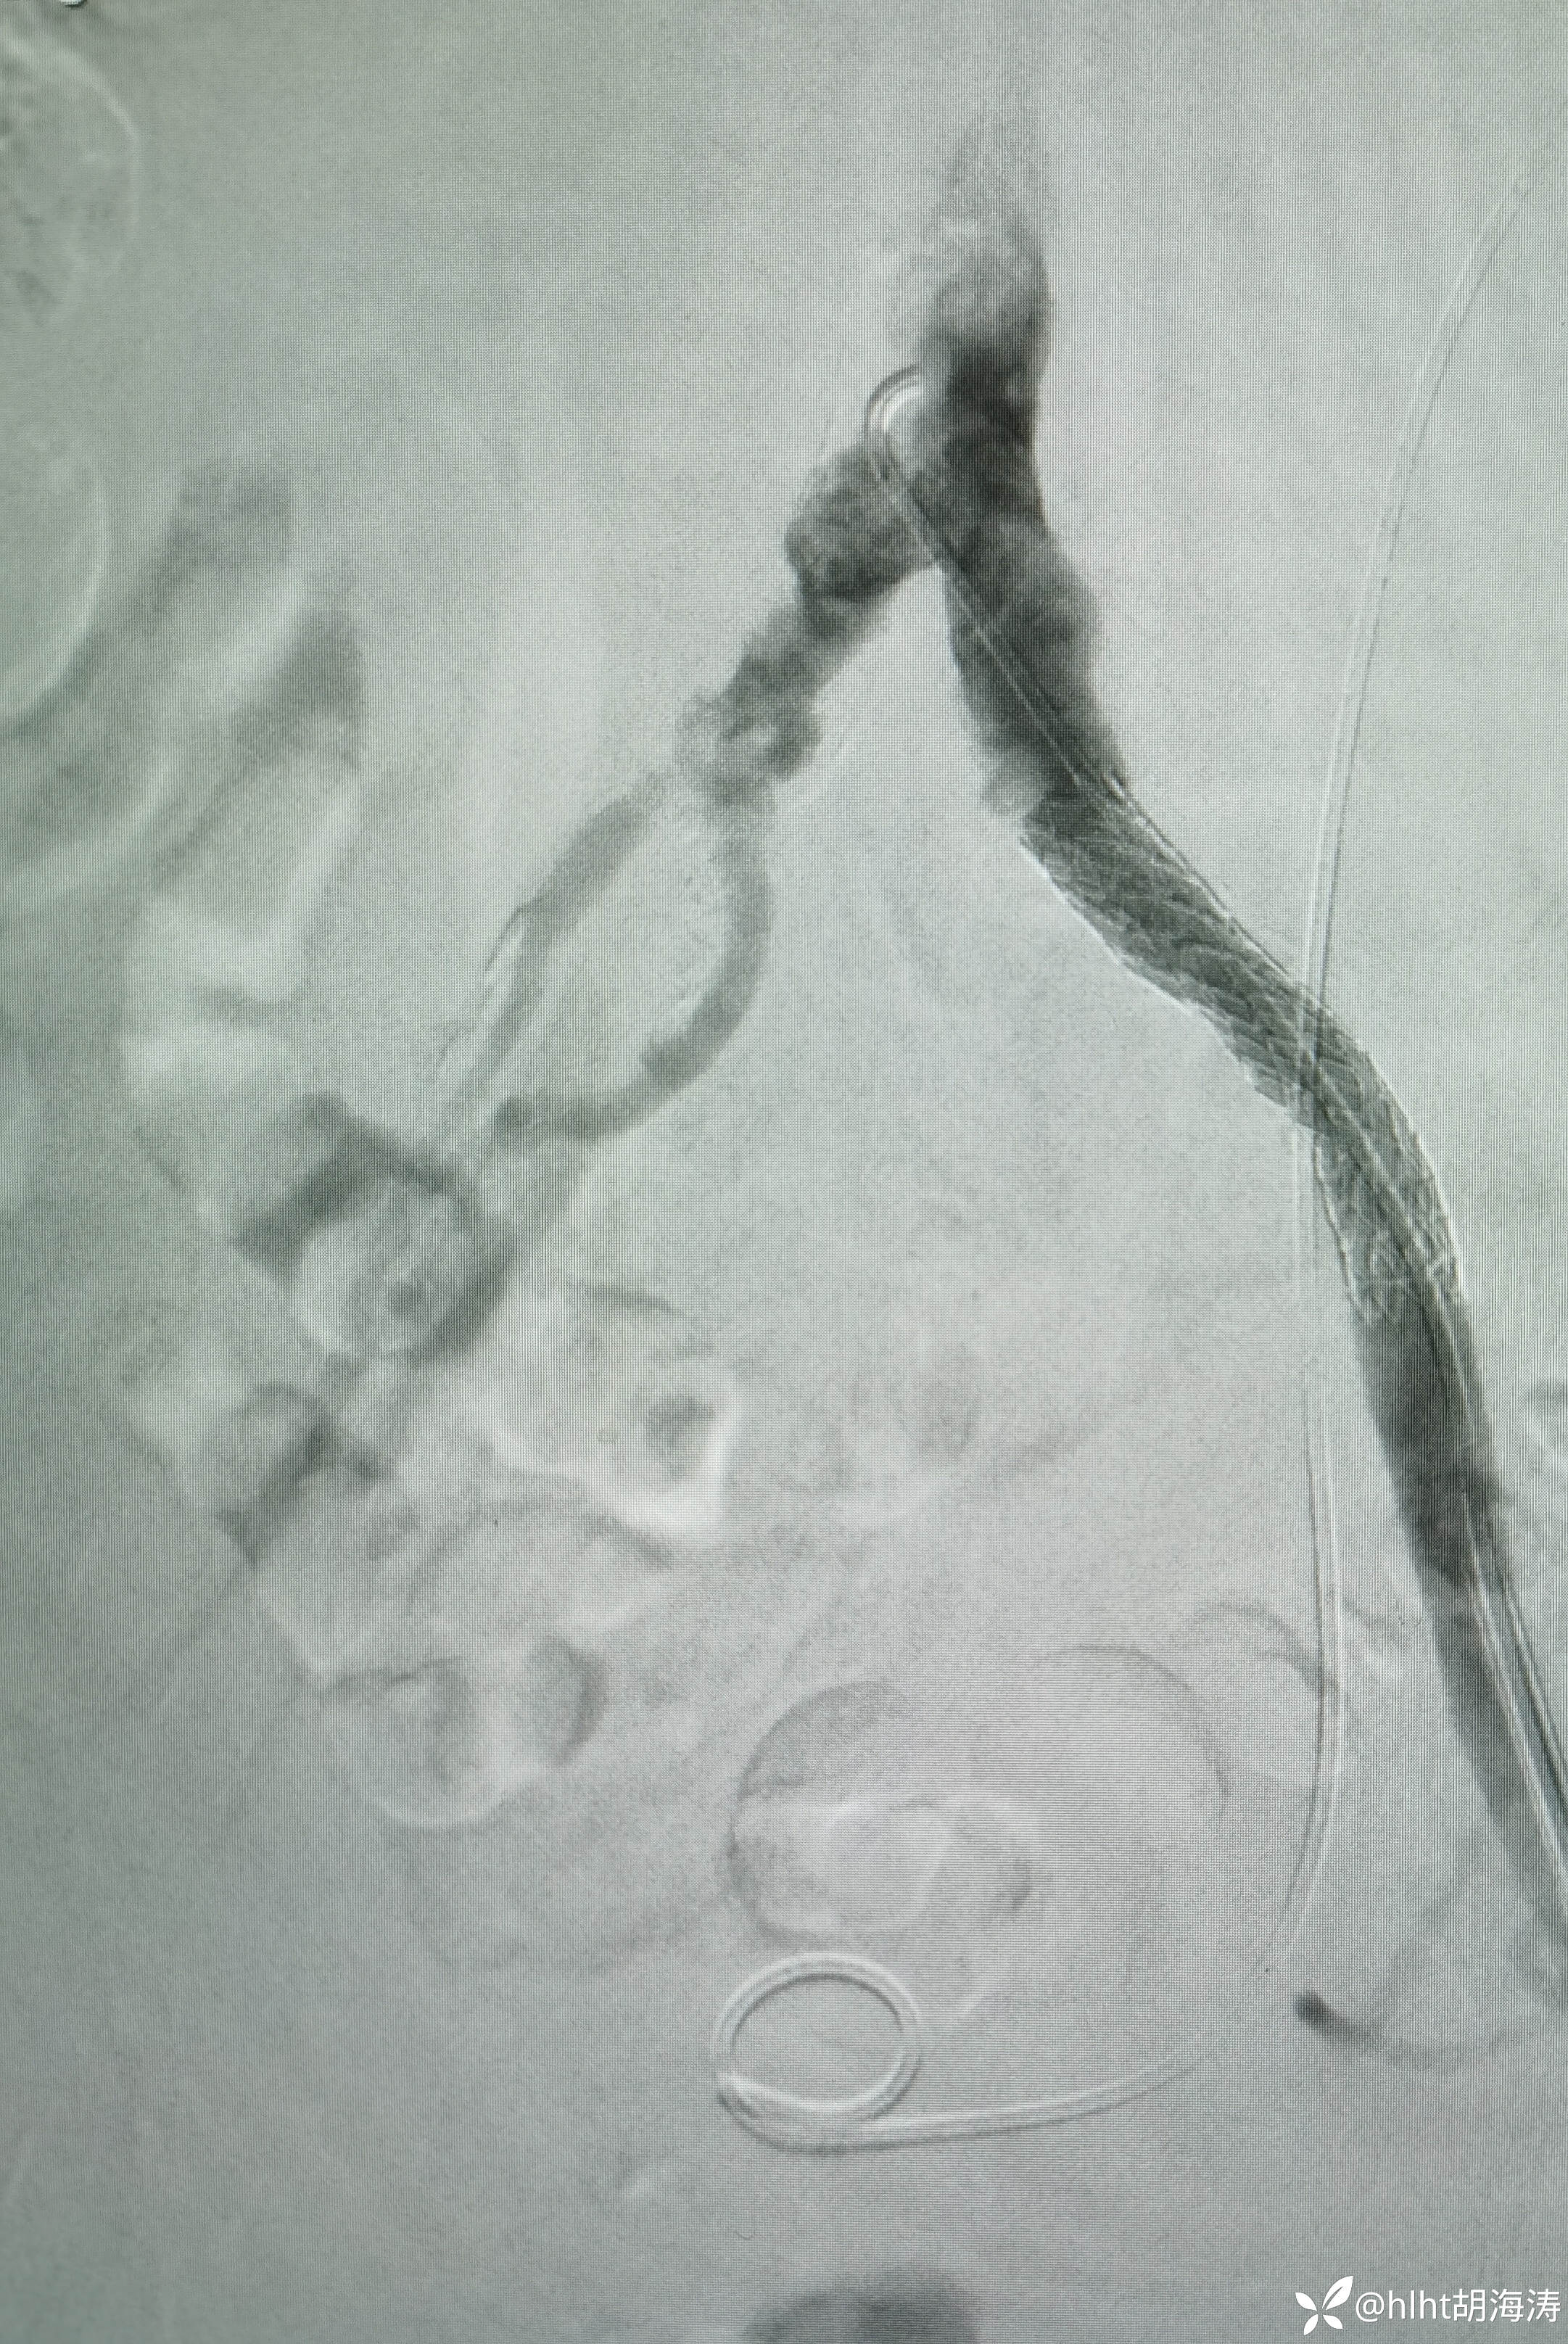

置入5F血管鞘:造影提示右侧髂外开口处重度狭窄

右侧髂外动脉直径不到左侧的1/2,扩到5mm,血流好,无限流夹层

右侧股浅很细,中远段闭塞导丝没法过,考虑髂外通了,循环也会改善: